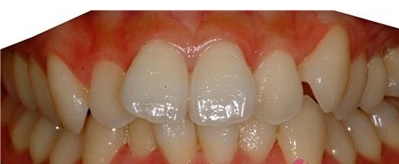

治疗前的牙齿照片。

因为牙齿太不齐了,所以决定做牙齿矫正治疗了。

先做了牙齿不齐矫正治疗,